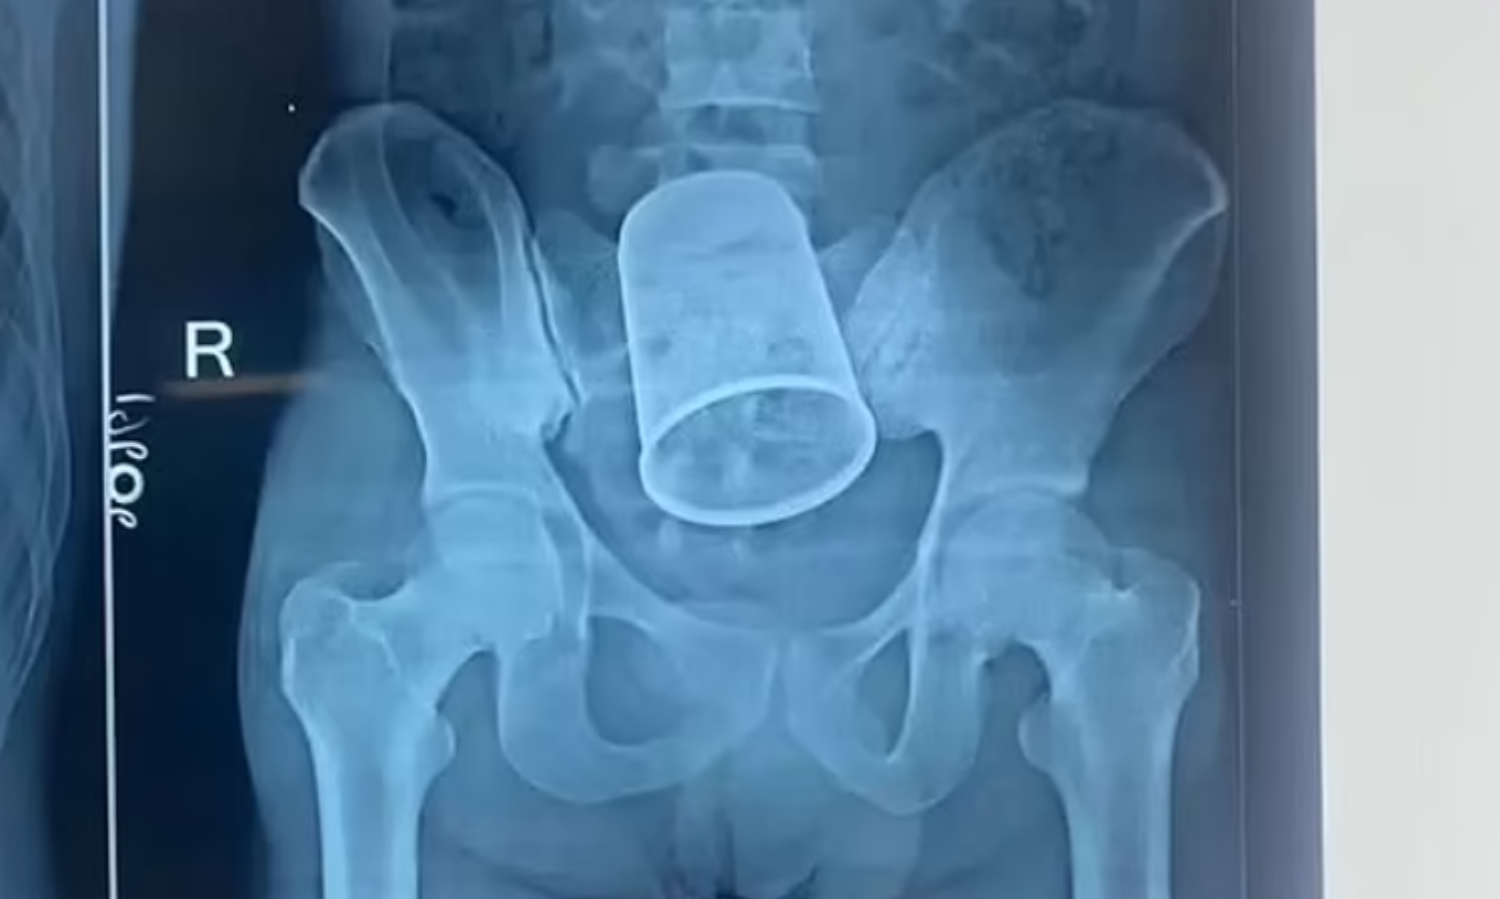

യുവാവിന്‍റെ വയറ്റില്‍ കുടുങ്ങിയ സ്റ്റീല്‍ ഗ്ലാസ് ശസ്ത്രക്രിയയിലൂടെ പുറത്തെടുത്തു

പാറ്റ്ന: യുവാവിന്‍റെ വയറ്റില്‍ കുടുങ്ങിയ സ്റ്റീല്‍ ഗ്ലാസ് രണ്ടര മണിക്കൂര്‍ നീണ്ട ശസ്ത്രക്രിയയിലൂടെ പുറത്തെടുത്തു. പാറ്റ്ന, ബേട്ടിയ സ്വദേശിയായ റിതേഷ് കുമാറിന്‍റെ(22) വയറ്റില്‍ നിന്നാണ് ഗ്ലാസ് പുറത്തെടുത്തത്. 5.5 ഇഞ്ച് വലിപ്പമുള്ള ഗ്ലാസാണ് വയറ്റില്‍ കുടുങ്ങിയത്.

ശക്തമായ വേദനയെയും രക്തസ്രാവത്തെയും തുടര്‍ന്ന് ഒക്ടോബര്‍ 4നാണ് റിതേഷിനെ പാറ്റ്ന മെഡിക്കല്‍ കോളേജ് ആശുപത്രിയില്‍ പ്രവേശിപ്പിച്ചത്. മദ്യപിച്ചെത്തിയ യുവാവിന്‍റെ ഗുഹ്യഭാഗത്ത് ചോരയൊലിക്കുന്നുണ്ടായിരുന്നു. ഗ്ലാസ് ഗുഹ്യഭാഗത്തു കൂടിയാണ് വയറിനുള്ളിൽ എത്തിയതെന്ന് ഡോക്ടർമാർ പറഞ്ഞു. ശസ്ത്രക്രിയ അപകടകരമായിരുന്നുവെന്നും എന്നാല്‍ 11 ഡോക്ടര്‍മാരടങ്ങുന്ന സംഘം സുരക്ഷിതമായി ഗ്ലാസ് പുറത്തെടുത്തുവെന്നും ശസ്ത്രക്രിയക്ക് നേതൃത്വം നല്‍കിയ ഡോ. ഇന്ദ്ര ശേഖര്‍ കുമാര്‍ പറഞ്ഞു.

എങ്ങനെയാണ് ഗ്ലാസ് വയറിനകത്ത് എത്തിയതെന്ന് അറിയില്ലെന്നാണ് റിതേഷ് കുമാർ ഡോക്ടർമാരോട് പറഞ്ഞത്. താൻ മദ്യപിച്ചിരിക്കുകയായിരുന്നെന്നും കപ്പ് വയറിനകത്ത് എത്തുകയും ഗുഹ്യഭാഗത്ത് മുറിവുണ്ടായി ചോരയൊലിക്കുകയും ചെയ്തതായി ഇയാൾ പറഞ്ഞു. അതേസമയം, ഇയാൾ ലൈംഗിക സുഖം ലഭിക്കുന്നതിന് ഗുഹ്യഭാഗ്യത്ത് കപ്പ് കയറ്റിയതാണെന്നാണ് ഡോക്ടർമാർ സംശയിക്കുന്നത്.ചിലർ ഇത്തരത്തിൽ ചെയ്യാറുണ്ടെന്നും ഇത്തരം അപകടകരമായ വസ്തുക്കൾ വയറിനുള്ളിൽ എത്താൻ സാധ്യത കൂടുതലാണെന്നും ഡോക്ടർമാർ പറഞ്ഞു. ശസ്ത്രക്രിയക്ക് ശേഷം യുവാവ് ആശുപത്രിയിൽ നിരീക്ഷണത്തിലാണ്.